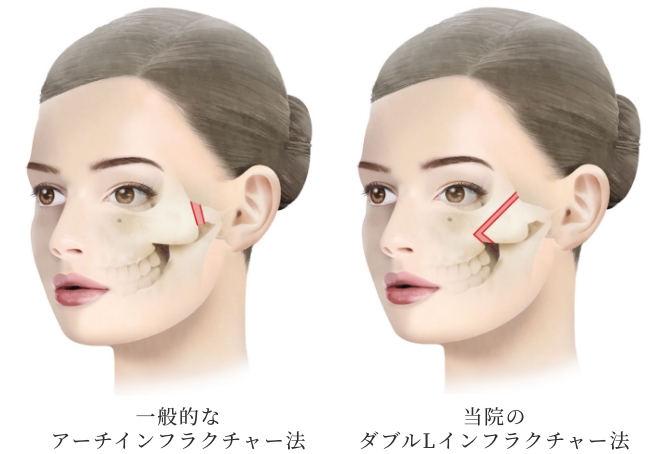

小木曽クリニックの

『頬骨形成骨切り術』の特徴

頬骨体部から弓(アーチ)

部に至る広範囲な骨切りが

可能

骨切り部位は頬骨弓部から体部前面に至り、L字型に長く幅広く切除し頬骨全体を内下方へ移動するため、頬骨全体に縮小効果があります。L字型に合計4回の骨切りが必要なため、複雑で精密な手技が必要な施術です。